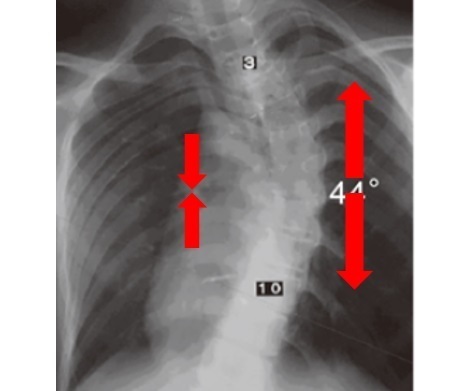

シュロス式のゲンシンゲン装具はかなりの矯正力があるのですが、運動療法では装具以上に側弯変形を矯正できます。

どのぐらい矯正をするかですが、年齢や側弯の程度にもよりますが多くの場合、過矯正(オーバーコレクション)するところまで背骨を動かします。

過矯正とは「もともとある側弯変形を逆転させる」ところを目標に矯正します。

おそらく多くある側弯症治療でも過矯正までできるものはシュロス法のみだと思います。

運動療法で過矯正まですることで、側弯症の矯正を可能とし、装具治療の効果もより高めることが可能になります。